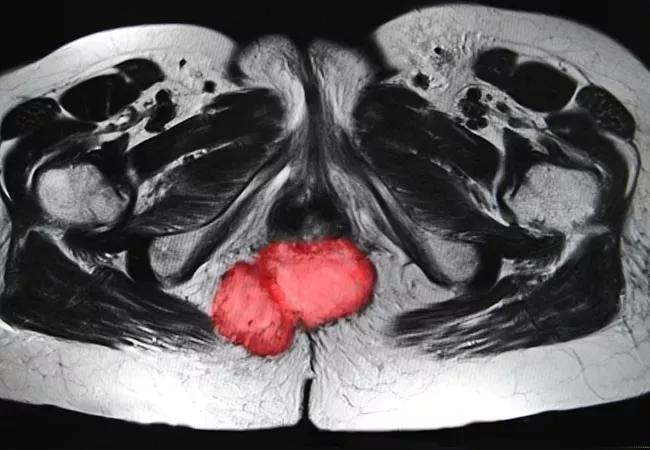

Preoperative Pelvic Radiation is Safe, Effective in Patients with IBD and Rectal Cancer

Preoperative pelvic radiation (XRT), with or without concurrent chemotherapy, is safe and effective in patients with inflammatory bowel disease (IBD) and locally advanced rectal cancer, according to Cleveland Clinic research presented at the 2019 American Society for Radiation Oncology (ASTRO) annual meeting.

IBD is a risk factor for the development of rectal cancers, and IBD patients are frequently diagnosed with locally advanced cancers.

“Patients who have IBD are at a higher risk of developing rectal cancer compared to the general population, and also tend to have worse prognoses with locally-advanced cancers,” says Cleveland Clinic radiation oncologist Sudha Amarnath, MD, the study’s lead author.

The retrospective study included 15 patients with IBD (nine with Crohn’s disease and six with ulcerative colitis) and AJCC stage II-IVA adenocarcinoma of the anorectum who underwent preoperative XRT (25 Gy/5fx) or chemo-XRT (capecitabine or CI-5FU and 50-50.4 Gy/25-28fx) between January 2014 and December 2018. The patients were followed for four to 33 months (median 17 months).